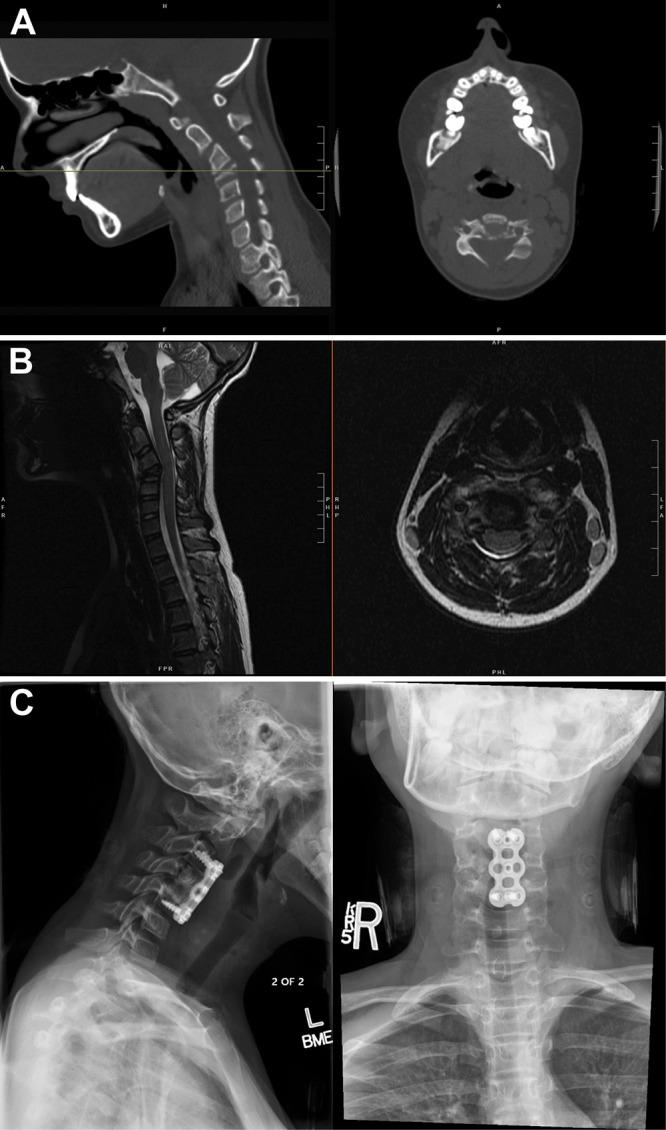

Fifty-six pediatric patients with clinical and radiographic evidence of CRMO were identified and clinical, radiographic, laboratory, and histopathological data were reviewed. All were evaluated via Jansson and Bristol CRMO diagnostic criteria. Ten had radiographic evidence of vertebral involvement (17.9%). Nine of these had multifocal disease. Five patients had multiple vertebrae affected. Six patients were evaluated for possible surgical intervention and one required intervention due to vertebra plana leading to a progressive kyphotic deformity and significant spinal canal stenosis.

确定了56例有CRMO临床和影像学证据的儿科患者,并回顾了其临床、影像学、实验室和组织病理学数据。所有患者均通过扬松和布里斯托尔CRMO诊断标准进行评估。其中10例有椎体受累的影像学证据(17.9%)。其中9例有多灶性病变。5例患者有多个椎体受累。6例患者接受了可能的手术干预评估,1例因椎体扁平导致进行性后凸畸形和严重椎管狭窄而需要干预。